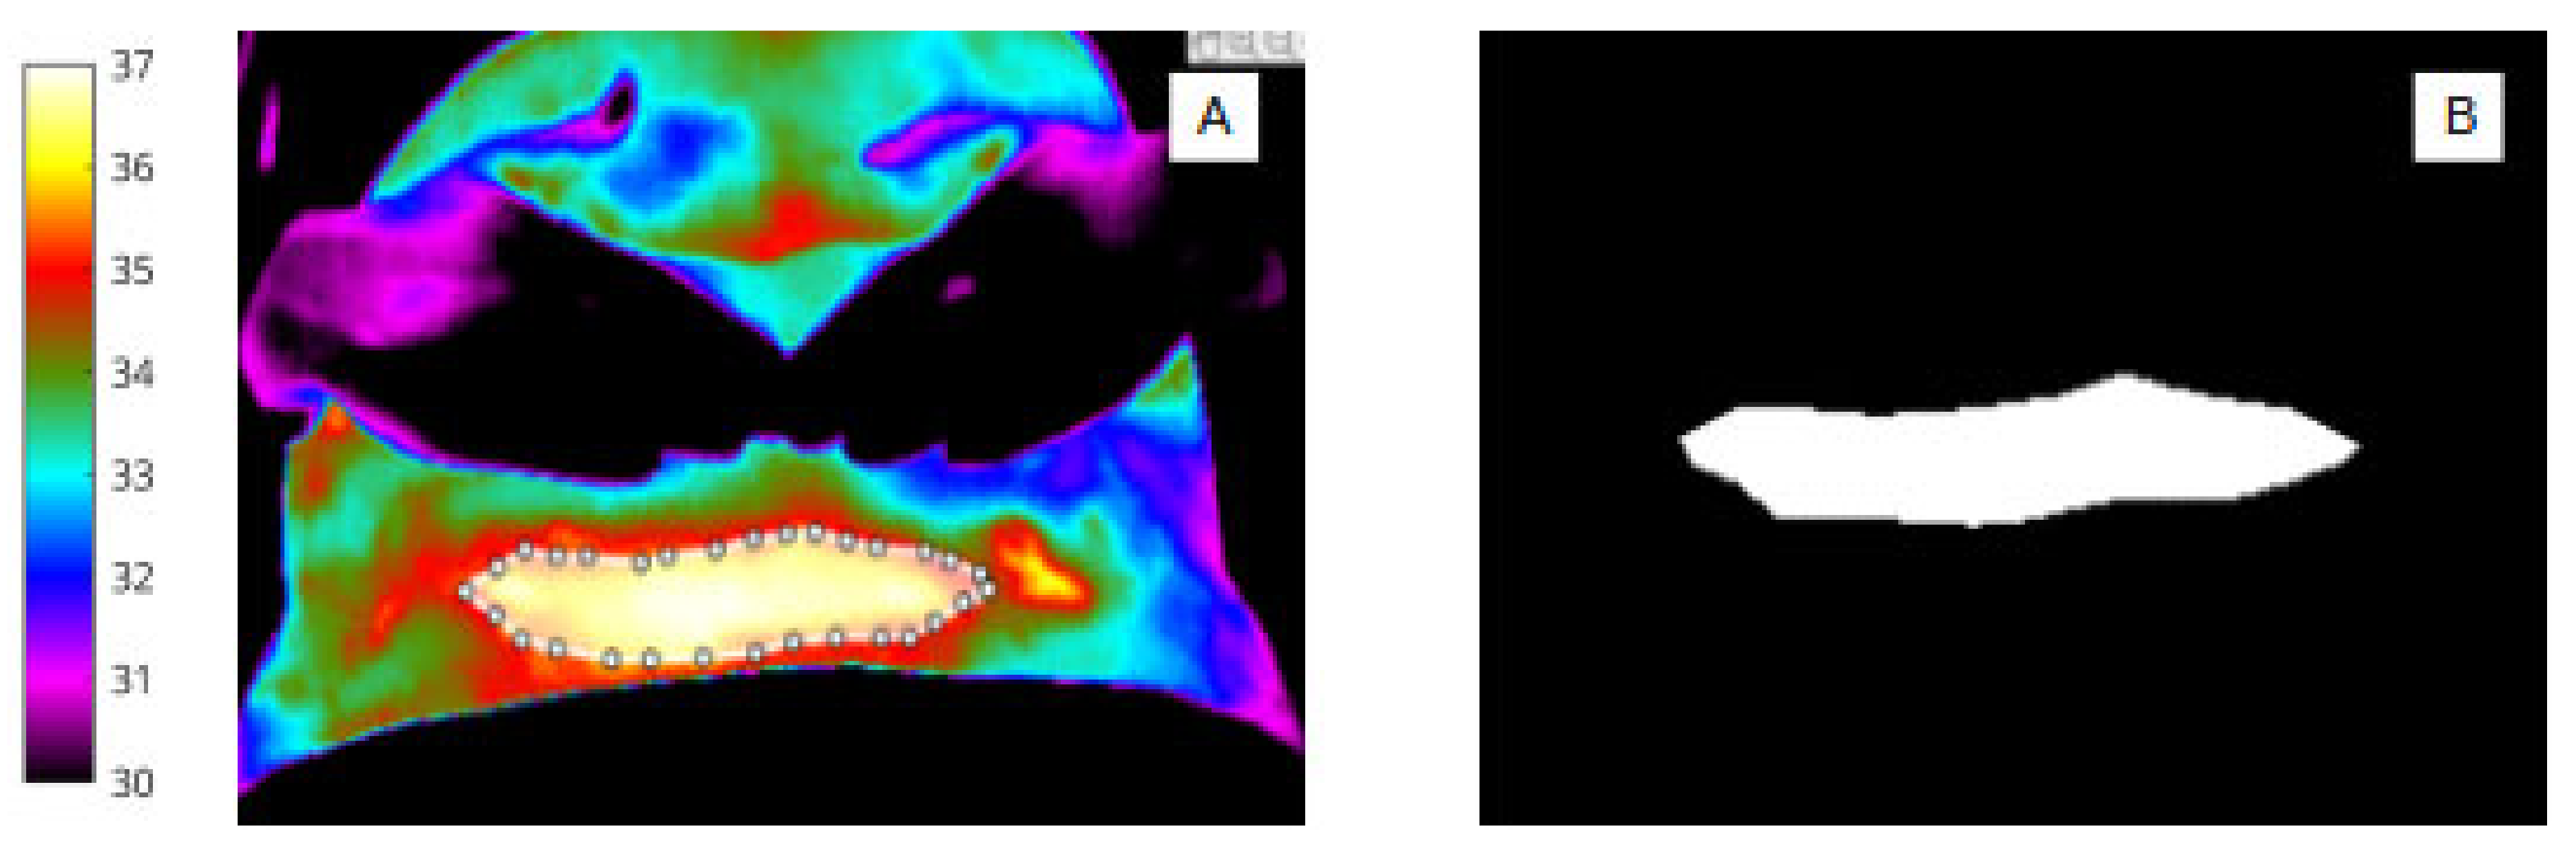

Figure 3.

(A) Pixel-based wound segmentation (ROI 2). (B) Binary mask of wound region (ROI 2).

2.4. Abdomen and Wound Segmentation

For abdomen (Figure 2A,B) and wound segmentation (Figure 3A,B), the respective regions were identified in infrared and the ROI was selected and cropped. With respect to the surgical site, ROI 2, determining the extent of the area, was often difficult to identify in infrared due to lack of clear anatomical landmarks. To help discern wound area from surrounding healthy skin, reference was made to the corresponding digital image.